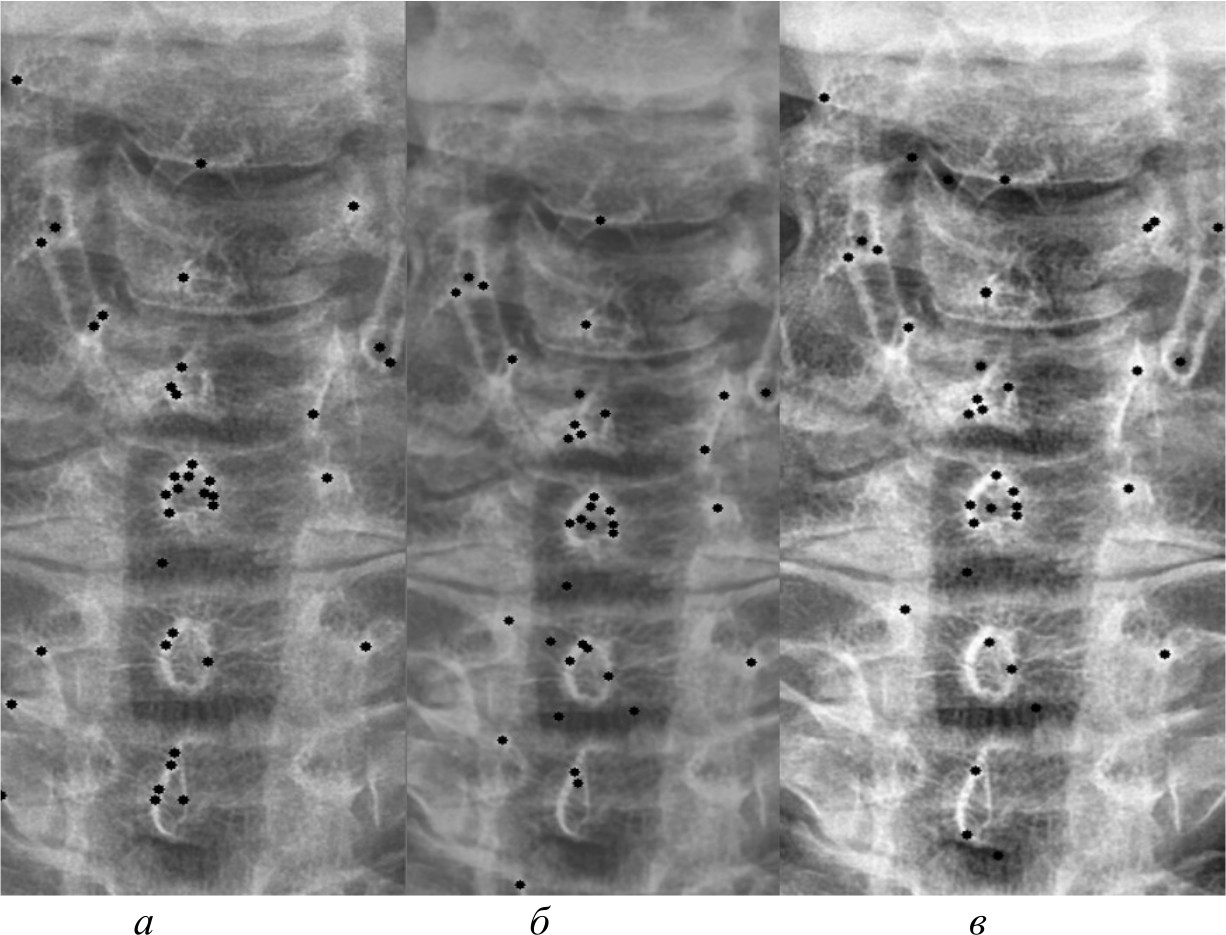

На рис. 4, 5 и 6 представлены результаты работы детектора Харриса, алгоритма Shi-Tomasi и SIFT при различных методах предварительной обработки изображений.

Рис. 5. Результаты работы алгоритма Shi-Tomasi на изображении, полученном при помощи специализированного программного обеспечения (а); результаты работы алгоритма Shi-Tomasi при методе базового отображения в Python (б); результаты работы алгоритма Shi-Tomasi при методе базового отображения Python с применением медианного фильтра (в); результаты работы алгоритма Shi-Tomasi при методе адаптивной эквализации гистограммы (г); результаты работы алгоритма Shi-Tomasi при методе стандартной эквализации гистограммы (д); результаты работы алгоритма Shi-Tomasi при методе гамма-коррекции (е)

Рис. 6. Результаты работы алгоритма SIFT на изображении, полученном при помощи специализированного программного обеспечения (а); результаты работы алгоритма SIFT при методе адаптивной эквализации гистограммы (б); результаты работы алгоритма SIFT при методе стандартной эквализации гистограммы (в)